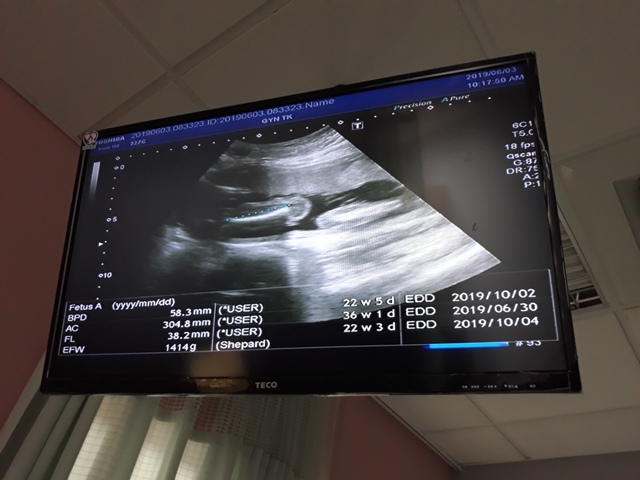

| 仙人掌(2019/06/03)的真心話 星期一 天氣晴 編號19-145 |

早上十點左右,和小純至澄清醫院做產檢,今日要做的是『妊娠糖尿病』的檢查(一般來說,妊娠糖尿病是24週 - 28週檢查,不過小純今天是第23週又3天,還沒到24週),首先我們先到抽血室去,護理師拿了五瓶裝的美達妍注射液讓小純喝,喝完之後一個小時以後再進行抽血。來之前小純有跟我說過,驗妊娠糖尿病要喝很甜的 糖水,但她今天喝了,感覺還好,不會很甜。

近五次產檢資料統計

| 日期/項目 | BPD | AC | FL | EFW | 心跳 |

| 2019年03月04日 | 無資料 | 無資料 | 無資料 | 無資料 | 無資料 |

| 2019年04月01日 | 28.9mm | 77.9mm | 14.2mm | 107g | 153 |

| 2019年04月29日 | 41.7mm(44%) | 125.7mm(61%) | 28.9mm(103%) | 241g(125%) | 150 |

| 2019年05月22日 | 53.4mm(28%) | 160.6mm(28%) | 34.6mm(20%) | 408g(69%) | 150 |

| 2019年06月03日 | 58.3mm(9%) | 179.6mm(12%) | 38.2mm(10%) | 584g(43%) | 157 |

| BPD:胎兒頭骨橫徑 AC:胎兒腹圍的長度 FL:胎兒大腿骨的長度 EFW:胎兒的體重 括弧內百分比為較上次產檢的成長比例 | |||||

今天關醫師也把4月22日所做的羊膜穿刺及羊水晶片的報告拿給我們,一切都正常。